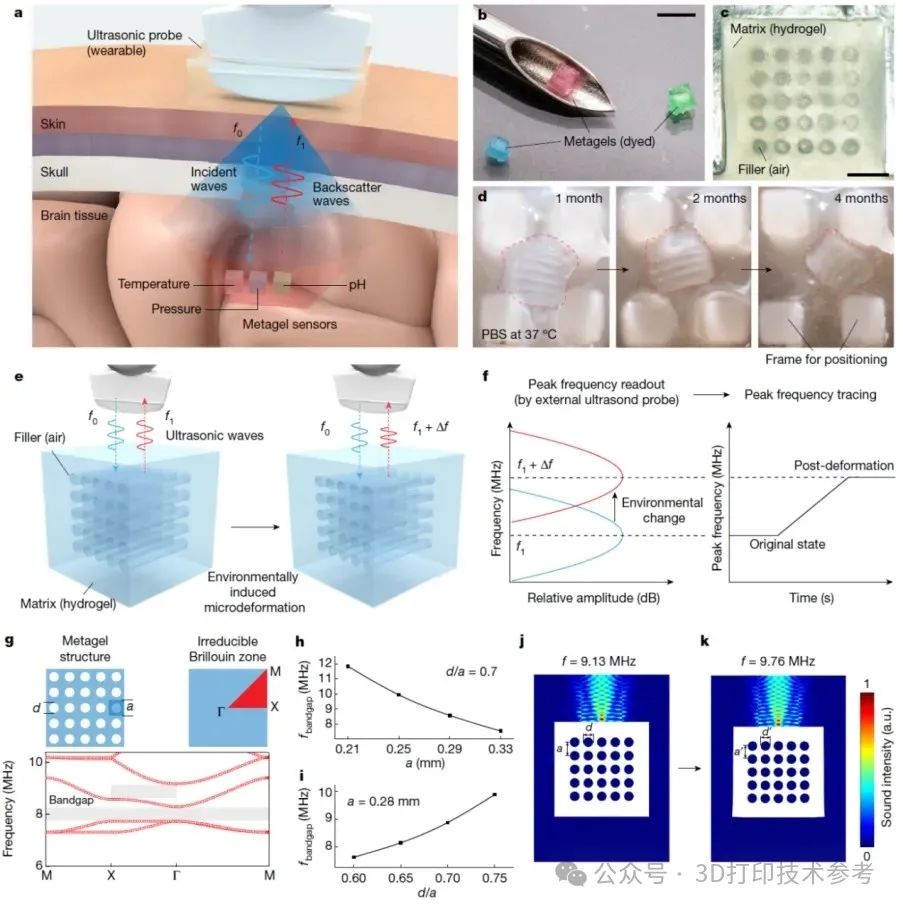

3D打印助力无线植入传感器制造

2024年6月,华中科技大学臧剑锋教授、姜晓兵教授以及新加坡南洋理工大学陈晓东教授团队携手合作,在《Nature》杂志发表了题为以"Injectable ultrasonic sensor for wireless monitoring of intracranial signals"的文章。

https://www.nature.com/articles/s41586-024-07334-y

研究人员开发出一种创新型可注射超声凝胶传感器。其由双网络交联的水凝胶基质和内部周期性排列的空气孔道组成,体积仅为2×2×2mm³。这种可注射传感器是研究团队采用摩方精密面投影微立体光刻(PμSL)3D打印技术(nanoArch® S140,精度:10 μm)加工模具后,经水凝胶翻模制备而成。经过计算机模拟结构优化,该特殊结构对入射超声波有很强的反射能力。

该传感器有望克服传统有线传感器存在的感染风险和术后并发症等问题,同时避免现有无线电子传感器体积过大、无法体内降解等临床应用挑战。(本部分来自摩方精密,引用已获授权。)